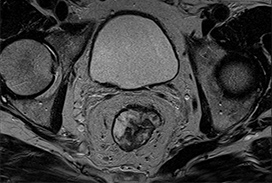

2023 London Imaging Discovery Day